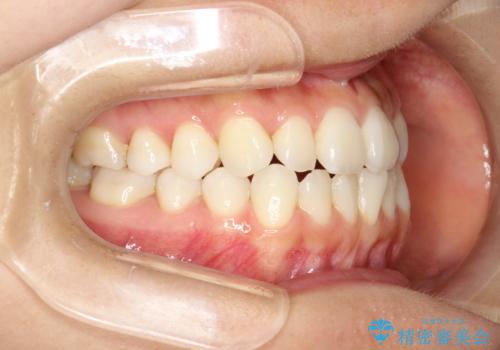

軽度の前歯のガタガタをインビザラインでの目立たない矯正

- 前歯のガタガタを主訴に来院されました。

軽度であったため、枚数制限のあるタイプのインビザラインのプランで治療することとしました。

軽度のガタガタを目立たずに手軽に矯正できるのもマウスピース矯正の魅力といえます。